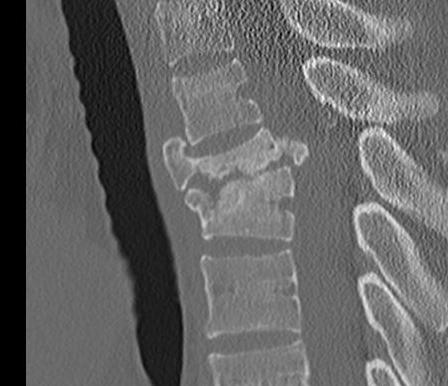

A. Comminution vertebral body on lateral X-ray

1. <30%

2. 30-60%

3. >60%

C. Deformity Correction

1. Kyphosis 3o or less

2. 4-9o

3. >10o needed